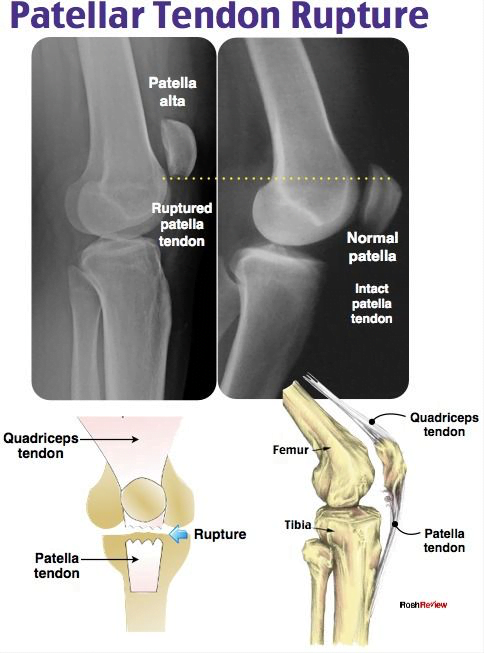

Quadriceps tendon tear

• Intense anterior knee pain

• A close-up of a x-ray of a kneeDescription automatically generated

Anterior Knee

• Osgood Schlatter’s

• Hoffa fat pad syndrome

• Quadriceps and patellar tendinopathy

• Bursitis